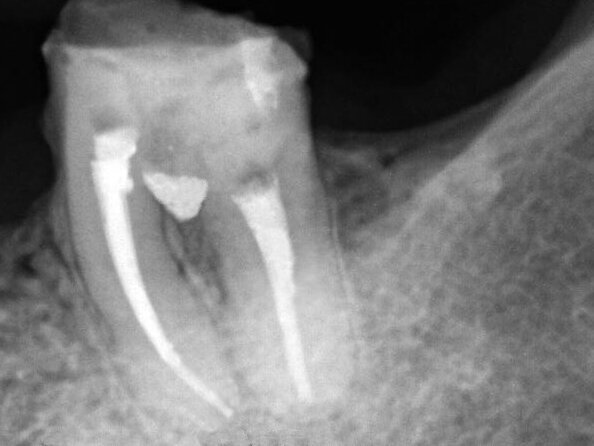

Female patient, 47 years old, presented with a clinical picture of extensive iatrogenic perforation of the furcation region of the dental element 36 (Figs. 1 and 2), associated with radiographic bone loss, vestibular fistula and pain on palpation. The patient reported history of having been previously subjected to an urgent intervention in this tooth by other professional, as it presented acute pain characteristic of pulpitis.

Fig. 1: Initial clinical and radiographic appearance of teeth 36

Fig. 2: Initial clinical and radiographic appearance of teeth 36